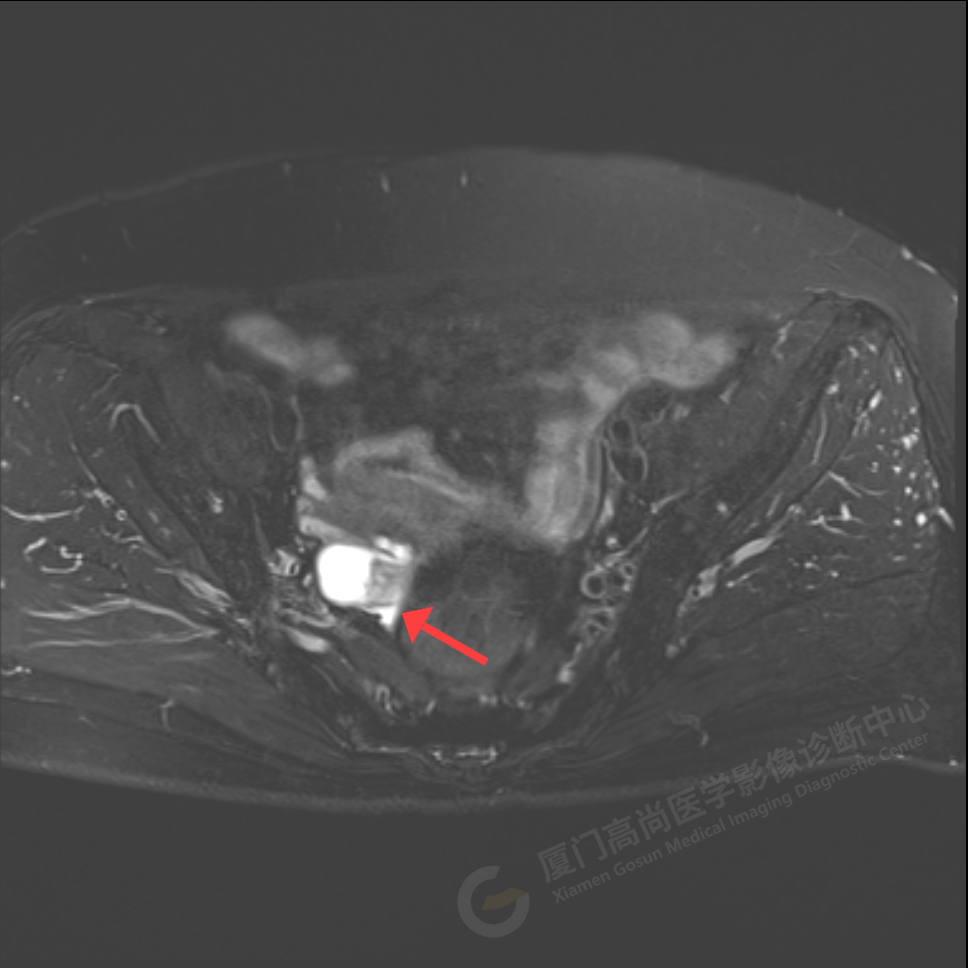

磁共振影像圖

我中心為陳阿姨安排了影像解讀及專家會診,經(jīng)過專家綜合分析,給出了初步診斷意見:右側(cè)附件區(qū)囊實性占位伴腫大淋巴結(jié),考慮卵巢來源惡性腫瘤,卵巢Ca可能性大。醫(yī)生建議盡快做進一步的檢查及就診。

陳阿姨家人經(jīng)過多方打聽和聯(lián)系,陳阿姨于5月18日至廣東中山大學附屬腫瘤醫(yī)院會診及手術,術后病理顯示:卵巢高級別漿液性癌2期,證實了高尚專家的判斷。